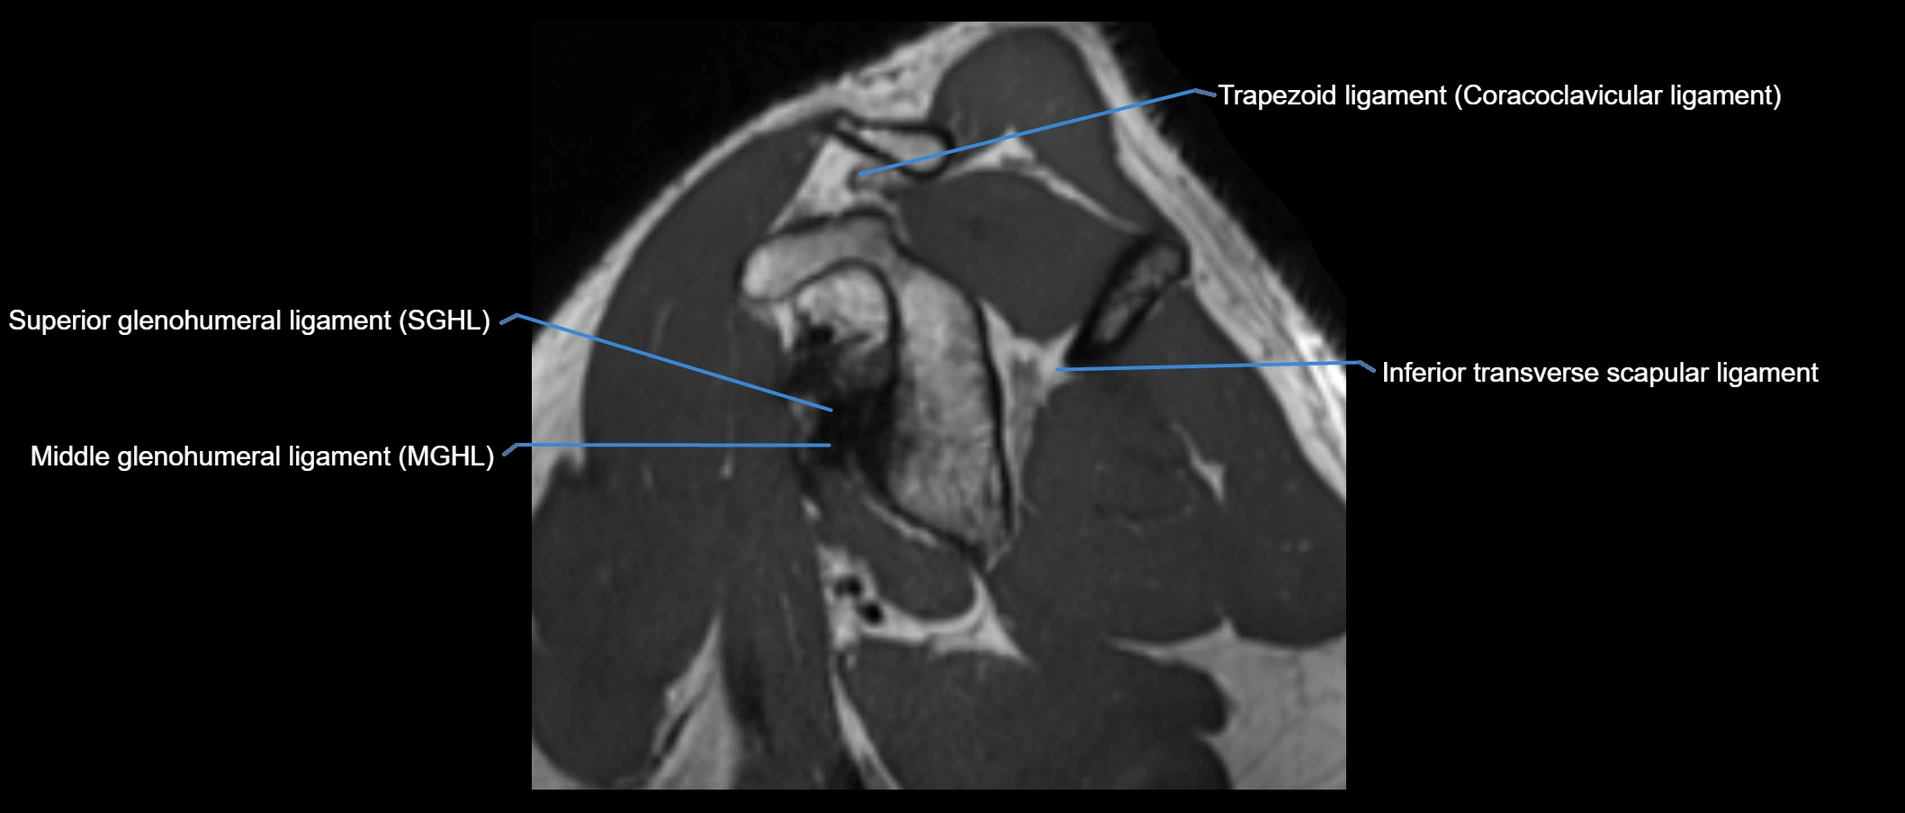

MRI images

image